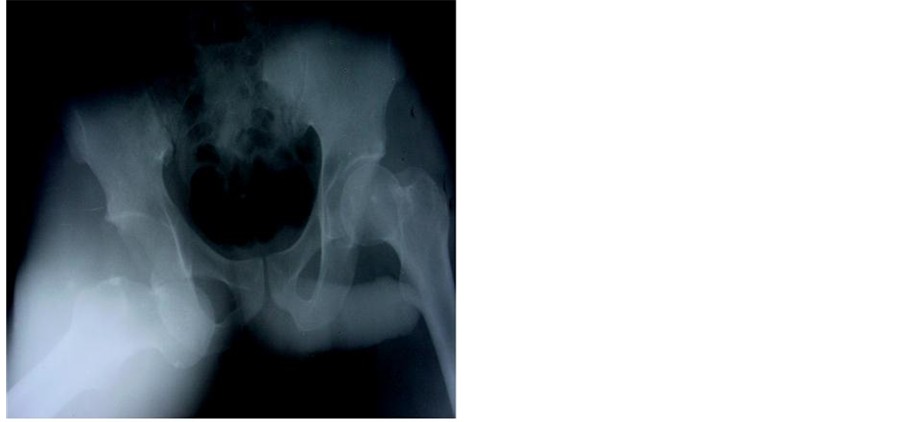

Mr. BA was a 29-year-old patient who was hospitalized in October 2000 following a road traffic accident. He was sitting behind the driver when his right knee hit the driver’s seat. On admission, the same limb was abducted, externally rotated and flexed at the hip. An anteroposterior radiograph of the pelvis revealed a right obturator dislocation (Figure 1) associated with a left supracondylar open fracture. Treatment consisted of closed reduction. The hip was stable afterward. The left supracondylar open fracture was treated surgically. Weight bearing on the dislocated limb was authorized after 6 weeks of bed traction. Thirty nine months later, the right hip is mobile, painless and normal on plain X-rays.

Figure 1. Anteroposterior X-ray of the pelvis showing a right obturator dislocation (patient 1).